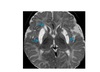

Highly vascular mass in nasopharynx eroding the medial ptyergoid plates and arising from sphenopalatine fossa?

Juvenile angiofibroma Supplied by the internal maxillary artery. Embolise it.